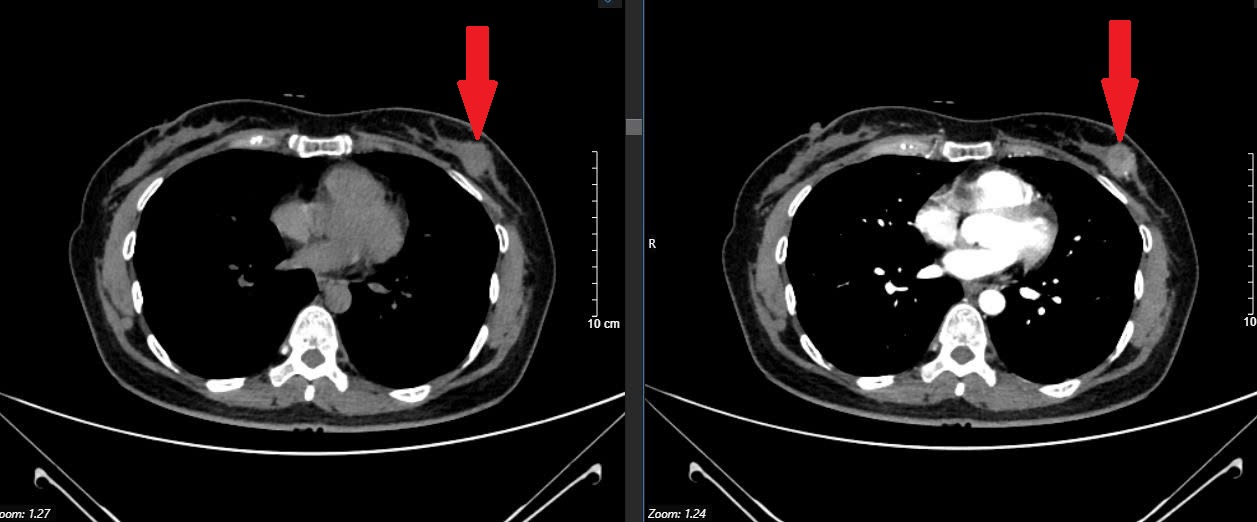

Kết quả siêu âm tuyến vú của chị cho thấy có dấu hiệu bất thường, bác sĩ tiếp tục chỉ định chụp nhũ ảnh (CT nhũ). Kết quả hình ảnh cho thấy tổn thương nghi ngờ ác tính, chị được khuyên nên sinh thiết để xác định chính xác. Lúc nhận thông tin, bệnh nhân thực sự bị sốc, vì không tin nổi mình lại mắc ung thư khi cơ thể vẫn khỏe mạnh bình thường.

Hình ảnh ung thư tại tuyến vú (BSCC).

Kết quả giải phẫu bệnh sau đó xác nhận ung thư vú giai đoạn sớm. May mắn, khối u chưa di căn và có thể phẫu thuật điều trị khỏi hoàn toàn. Sau phẫu thuật, chị P hồi phục tốt và vẫn duy trì sinh hoạt, làm việc bình thường.